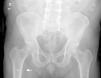

La mayoría de las ciáticas se deben a la compresión de raíces nerviosas lumbares, aunque algunas tienen origen extrarraquídeo, como en el síndrome de pinzamiento isquiofemoral. Se presenta el caso de un varón de 64 años con dolor ciático derecho de 10 años de evolución, exclusivamente al estar sentado. Fue sometido a múltiples cirugías por estenosis lumbar (L4-L5, luego L3-L4 y posteriormente L5-S1 con artrodesis hasta S1), además de infiltraciones y radiofrecuencia, sin mejoría. Las pruebas neurofisiológicas y de imagen no mostraron compresión significativa, salvo edema en la inserción isquiática del músculo cuadrado femoral. Tras una infiltración diagnóstica con anestésico local, el dolor desapareció temporalmente, confirmando el diagnóstico de síndrome isquiofemoral. Fue tratado mediante osteotomía del trocánter menor, con resolución completa del dolor y recuperación funcional. Este caso resalta la importancia de considerar causas extrarraquídeas en ciáticas persistentes tras cirugía vertebral.

Most cases of sciatica are caused by compression of lumbar nerve roots, although some originate from extraradicular structures, such as in ischiofemoral impingement syndrome. We present the case of a 64-year-old man with a 10-year history of right-sided sciatic pain occurring only while seated. He underwent several lumbar surgeries for spinal stenosis (L4–L5, then L3–L4, and later L5–S1 with fusion to S1), as well as multiple infiltrations and pulsed radiofrequency, without improvement. Neurophysiological and imaging studies showed no significant compression, except for edema at the ischial insertion of the quadratus femoris muscle. A diagnostic local anesthetic infiltration temporarily resolved the pain, confirming ischiofemoral impingement syndrome. He was treated with osteotomy of the lesser trochanter, achieving complete pain resolution and functional recovery. This case highlights the importance of considering extraradicular causes in patients with persistent sciatic pain after spinal surgery.